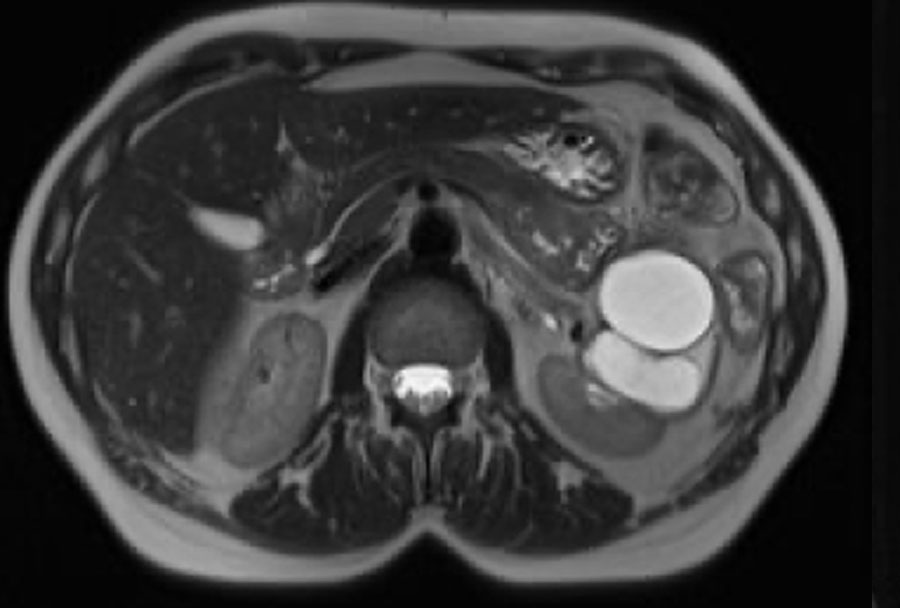

Có một khối dạng nang ở thận phải với nhiều (> 4) vách ngăn mỏng, nhẵn, có ngấm thuốc.

Tổn thương được phân loại là Bosniak IIF.